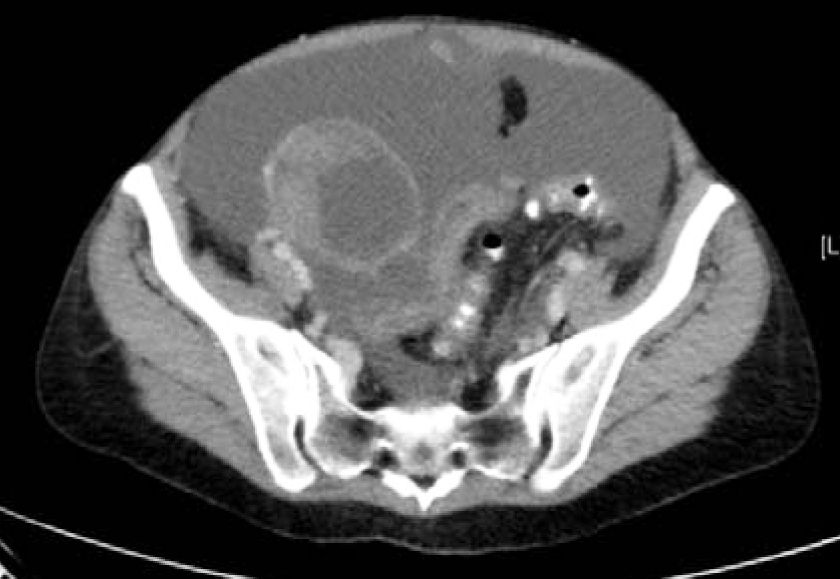

A 55-year-old female with recurrent Stage IIIA ovarian cancer, initially low malignant potential tumor with micropapillary features which then progressed to low-grade serous carcinoma. Patient was originally diagnosed with ovarian cancer in January 2009, after experiencing abdominal pain, nausea and vomiting. Since then, patient has had a complicated medical course with multiple hospitalizations throughout the years. Initial imaging revealed bilateral adnexal masses, omental lesion and ascites (Figure 4 and 5). A therapeutic and diagnostic paracentesis was performed and ascites fluid was positive for papillary serous ovarian tumor. A primary debulking surgery including a total abdominal hysterectomy with bilateral salpingo-oophorectomy, omentectomy, bilateral paraaortic and pelvic lymphadenectomy was performed. Initial pathology report revealed a 10cm tumor of the right ovary and a 15cm tumor of the left ovary, which were both positive for serous borderline tumor with micropapillary features. Small bowel implants and omentum were also positive for serous borderline tumor. Lymph nodes and appendix were negative. She was diagnosed with ovarian cancer with serous borderline tumor stage IIIA and completed six cycles of adjuvant chemotherapy with carboplatin and taxol.

Figure 4: CT scan abdomen and pelvis. Extensive splenic and liver implants.

Figure 5: CT scan abdomen and pelvis. Peritoneal implant medial to spleen measuring 24x26 mm.